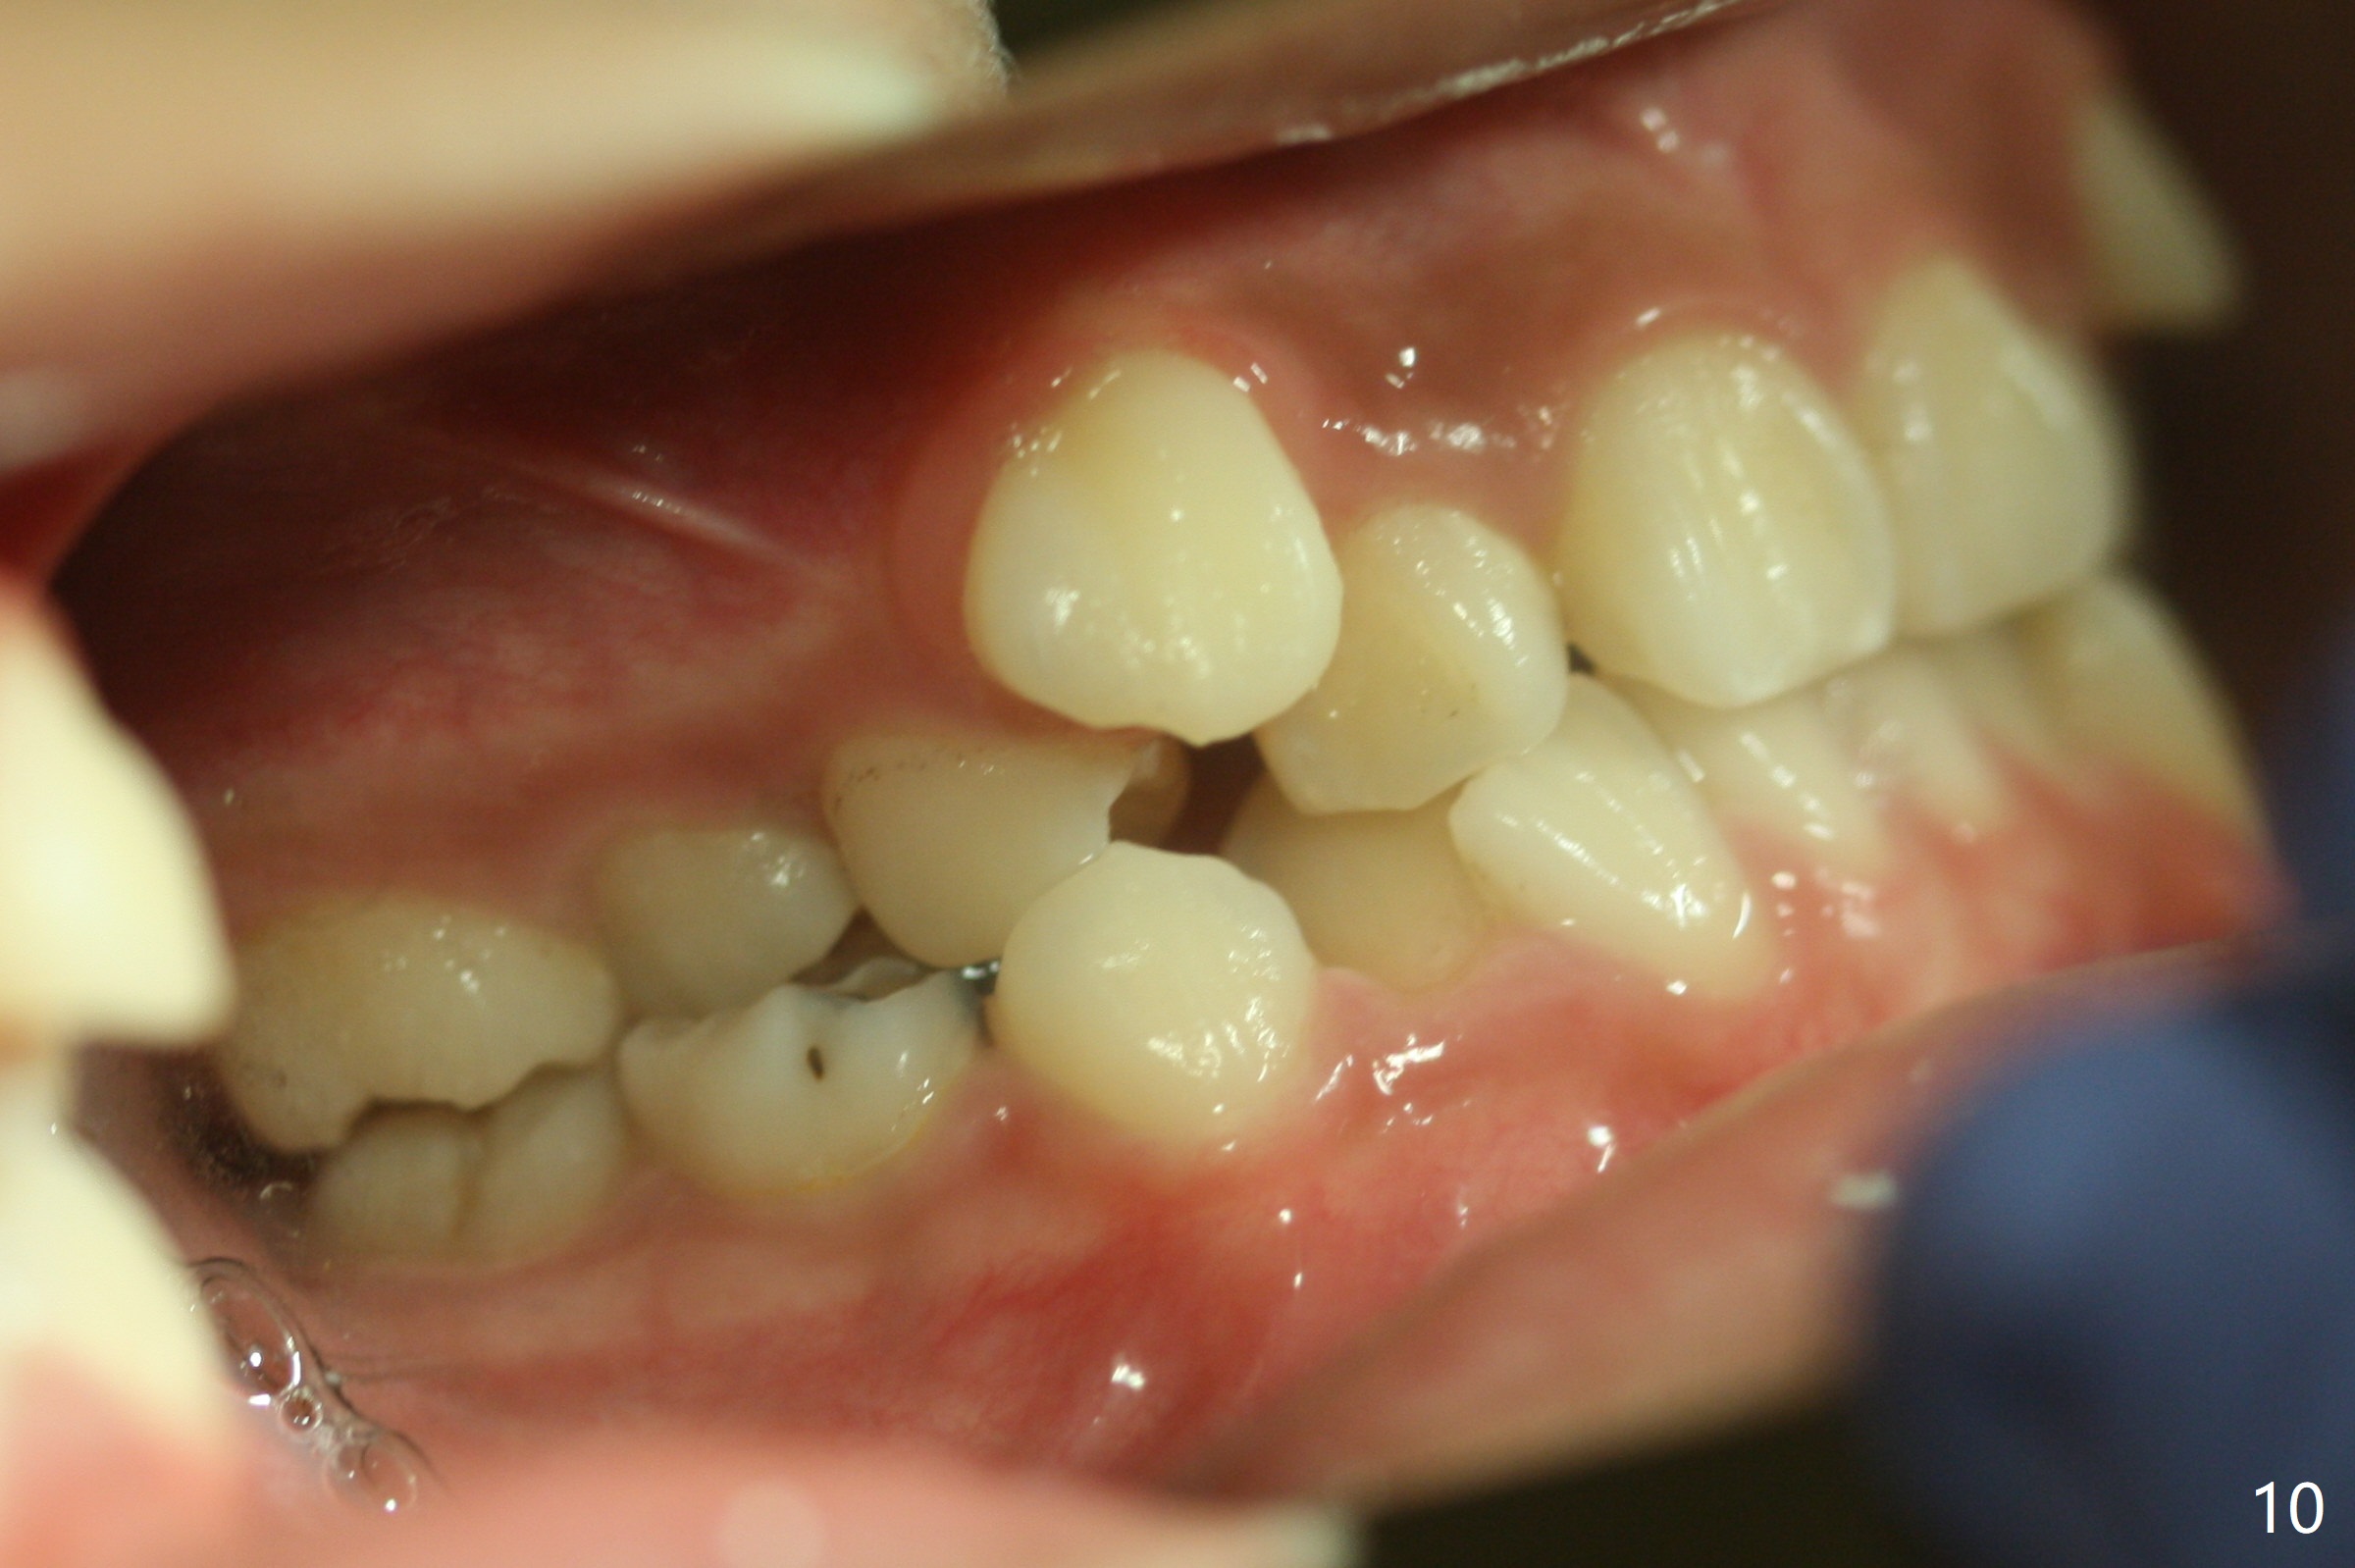

Severe crowding with normal facial profile appears to dictate extraction of 4 bicuspids and of the lower 2nd primary molars (Fig.1-11).  Since there is no time for banding before school, delay in orthodontic treatment post extraction will lose space?

Dear Dr. Shaughnessy: can you open the following link?  I would like to try to extract 4 bicuspids and 2 lower primary 2nd molars and let the canines shift by themselves.  But I wonder whether the 2nd permanent bicuspids, especially the upper ones, may shift mesially instead.  How would you like to handle the situation?

In fact, the family is moving out of state.  To accomplish automatic shifting before seeing a new dentist, extraction is executed.  At the mother's request, six teeth are removed.